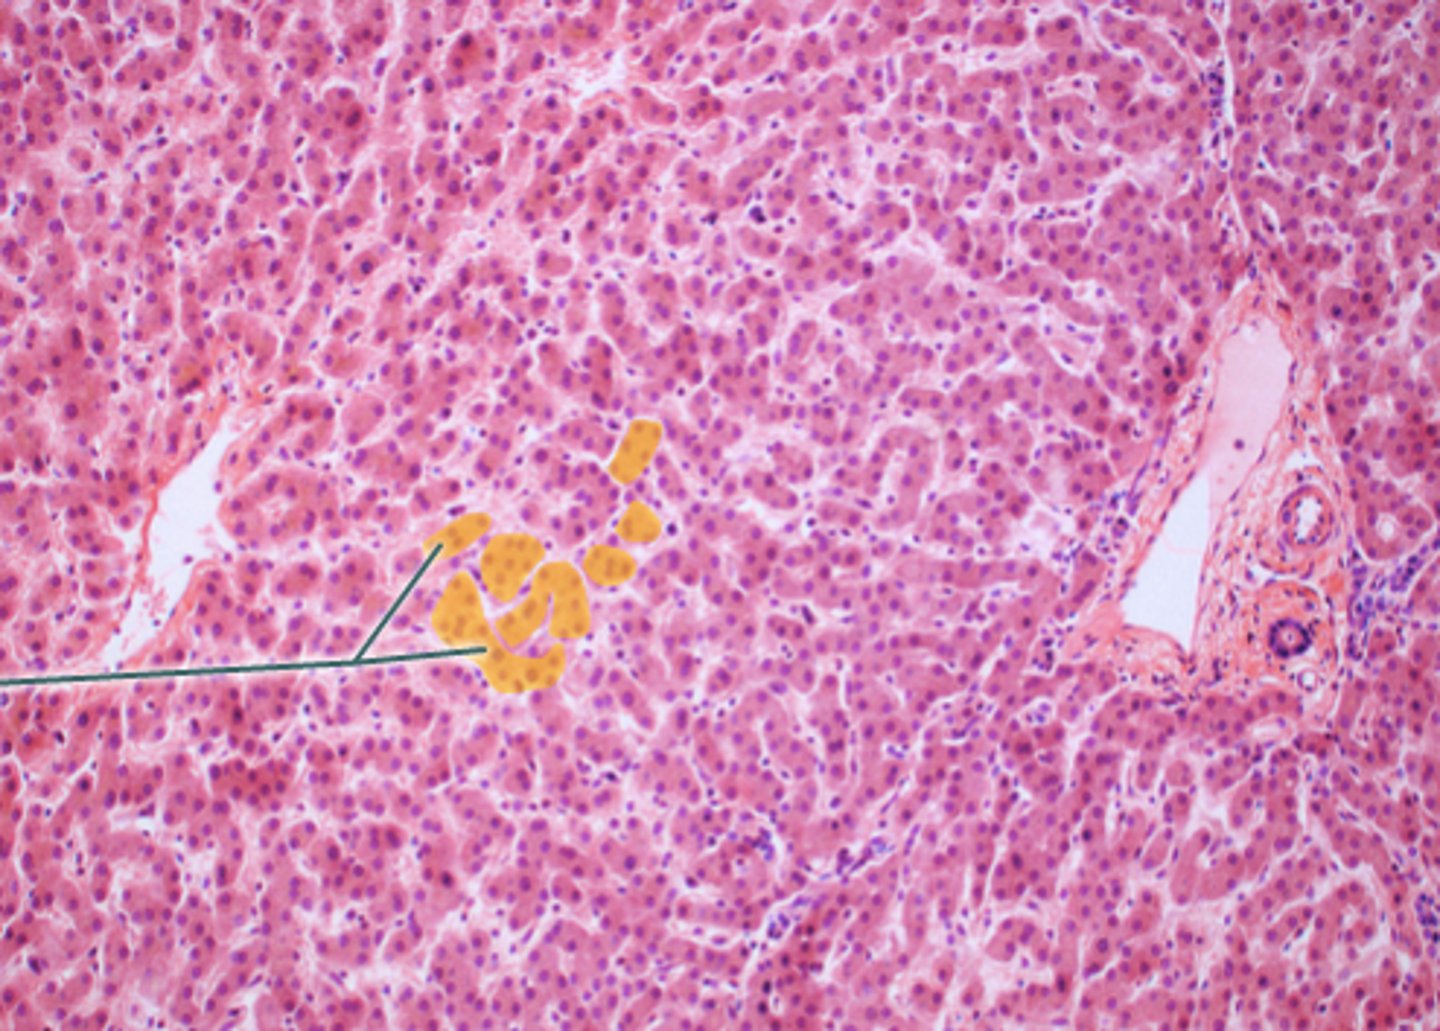

hepatocytes

hepatic triad

venule of hepatic portal vein

hepatic artery histo

bile collecting ducts histo